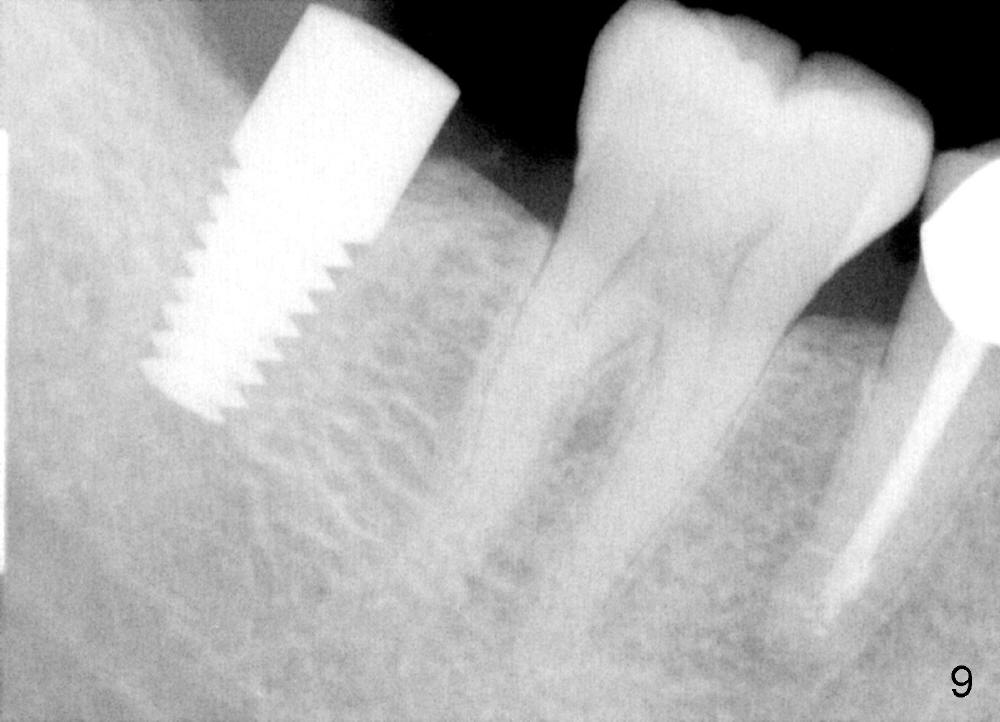

Bone density immediately next to the implant increases while the mesial lamina dura is disappearing 2.5 months postop or 18 months postop (Fig.9, as compared to Fig.1,7).